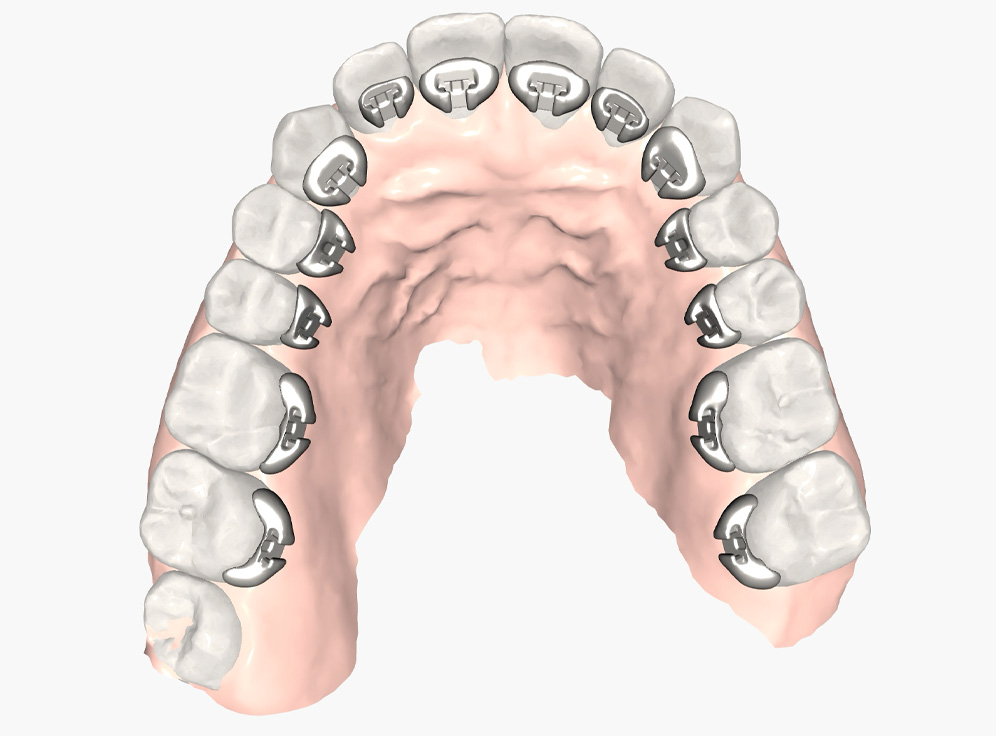

Today’s modern scanners utilize cameras and laser technology to quickly capture detailed images of the mouth. The scanned data is then processed to create a highly accurate digital model, which is used for diagnosis, treatment planning, and orthodontic appliance fabrication.

Digital scanners produce highly detailed 3D models, reducing errors and ensuring better-fitting appliances like custom braces, aligners, and retainers. They also eliminate distortions that are caused by patient moving or improper mixing of impression material.

In addition to aligners, one aesthetic treatment option that leverages the advanced technology of digital intraoral scanners is Brava braces, which are custom fit braces placed on the back side of each tooth where they remain hidden from view.